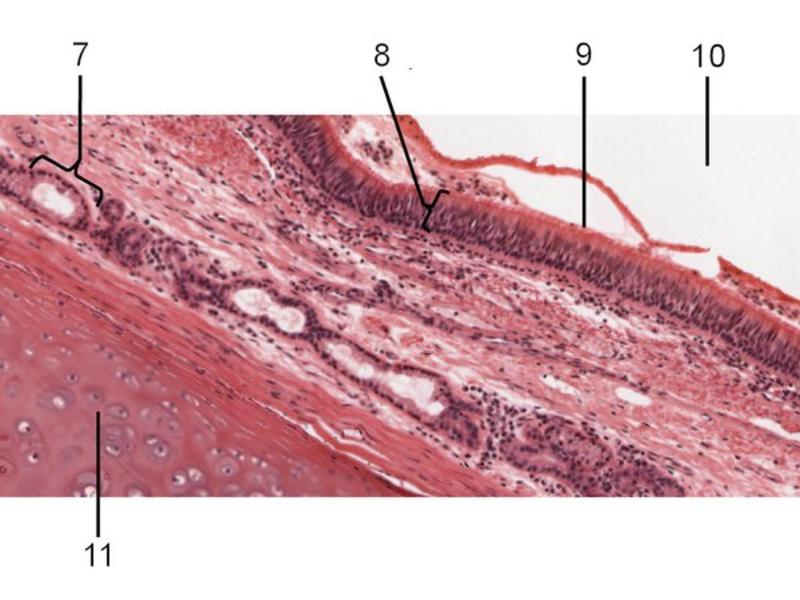

Slides: Respiratory System

- Slide 71: Nostril

Nostril

Trachea

Bronchi - Transitions

- Intrapulmonary bronchi

- Irregular cartilage

- Respiratory epithelium

- Glands